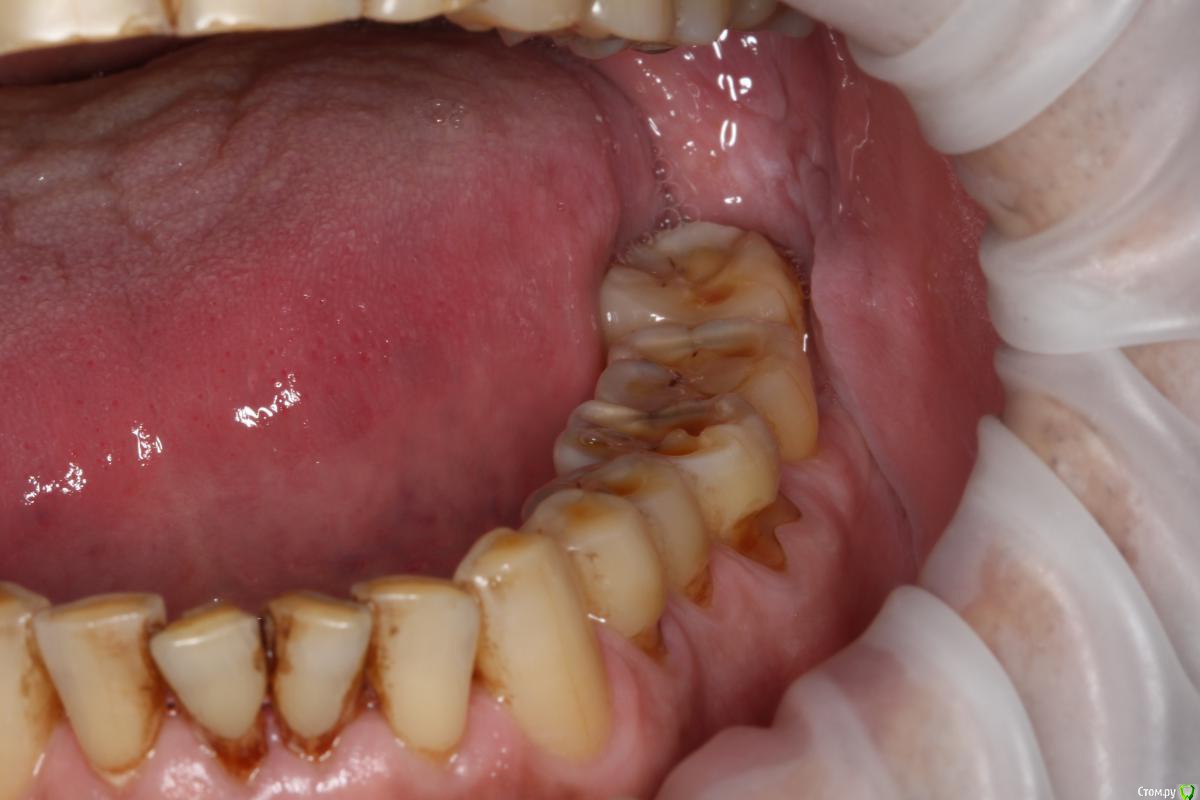

Robinbobin Опубликовано 27 марта, 2015 Поделиться Опубликовано 27 марта, 2015 (изменено) Пациент 57 лет с жалобами на стираемость зубов,чувствительность и бруксизм Хотелось бы услышать ваше мнение!!!! Изменено 27 марта, 2015 пользователем Robinbobin Ссылка на комментарий

SDC Опубликовано 27 марта, 2015 Поделиться Опубликовано 27 марта, 2015 (изменено) в планах сделать керамические жевательные и режущие края зубовА я бы в 57-летнем возрасте настаивал на комбинированных, с золотой окклюзионной поверхностью коронках с кольцевой гирляндой на все моляры и безметалл на топ 20.удаление 8-х http://s020.radikal.ru/i712/1503/33/4e3a55681950.jpg http://s003.radikal.ru/i204/1503/2b/6265c6920c6f.jpg Изменено 27 марта, 2015 пользователем SDC Ссылка на комментарий

DmitrySH Опубликовано 28 марта, 2015 Поделиться Опубликовано 28 марта, 2015 http://s003.radikal.ru/i204/1503/2b/6265c6920c6f.jpg Почему не цельнолитые? На молярах НЧ, в первую очередь, визуализируется жевательная поверхность. Эстетики от керамики вокруг, мы не получаем. В чем смысл? Ссылка на комментарий

carloss Опубликовано 28 марта, 2015 Поделиться Опубликовано 28 марта, 2015 А я бы в 57-летнем возрасте настаивал на комбинированных, с золотой окклюзионной поверхностью коронках с кольцевой гирляндой на все моляры и безметалл на топ 20.удаление 8-х http://s020.radikal.ru/i712/1503/33/4e3a55681950.jpg http://s003.radikal.ru/i204/1503/2b/6265c6920c6f.jpgсколы керамики тут обеспечены.. да и по эстетике, лучше уж цельнозолотые Ссылка на комментарий

Robinbobin Опубликовано 28 марта, 2015 Автор Поделиться Опубликовано 28 марта, 2015 сколы керамики тут обеспечены.. да и по эстетике, лучше уж цельнозолотые Дело в том что пациент отказывается точить зубы и мы решили сделать оклюзионные накладки из прессовонной керамики Ссылка на комментарий